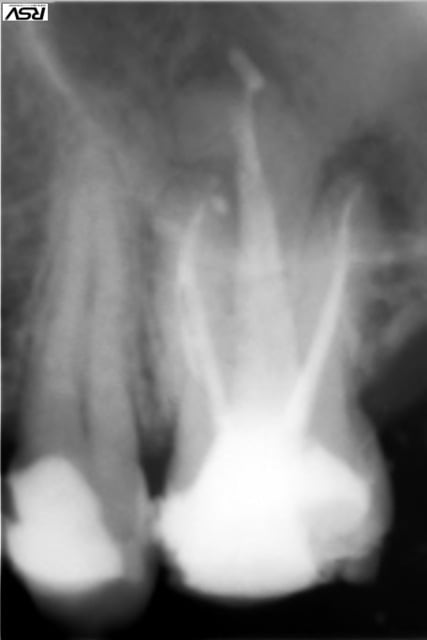

bin tiens je profite du wagon: celui ci ne part pas a l'étranger mais débarque de Russie et me causera peut être soucis:

26 douloureuse, à la radio nécrose et trois pêches. Pas de prescriptiuon atb, traitement radiculaire classique, juste irrigation peut être un peu plus insistante que d'hab, pas de suintement terminal, tout ok, obturation.( leger manque de condensation mv2 mais bon...une seule sortie apex alors je zappe).

semaine suivante, tout bien comme y faut pour rassurer, pas de suites, même pas de douleurs post op, suis tout content. le délabrement et les parois résiduelles m'incitent a ancrer en palatin, tout va bene, jusqu'au moment ultime lors du scellement de l'ancrage: légère et fugace "sensation patient" à l'insertion du pivot dans le ciment de scellement.......grrrr....je me questionne mais le temps que je me réponde une certaine forme de fatalisme me fait poursuivre et terminer.

Allez, soyons optimiste, grand, petite poussée du cone de gutta palatin quand tu as bidouillé ton logement de tenon?

J'ai dû abimer ma gutta et reperméabiliser le canal lors de la préparation du logement, ça c'est "silencieux", l'enduction de ciment est silencieuse aussi évidemment, et c'est a l'insertion que j'ai dû provoquer comme un effet de piston au bout...la constriction apicale était déjà pas belle, je me demande ce que j'ai pu y balancer à ce moment là.

mauvaise décision prise en 2 secondes, simplement parce que je n'ai pas voulu reconnaitre le risque et remettre en cause ce que je croyais être un succès...je le revois la semaine prochaine, mais comment savoir, ce genre de truc va évoluer a bas bruit...